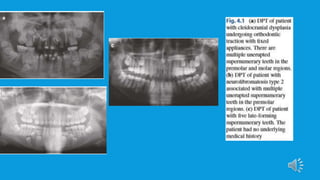

 Supernumerary teeth can occur singly, in multiples, unilaterally or bilaterally and

in either the maxilla or mandible.

 Studies show that the majority of patients present with one or two

supernumerary teeth. Multiple supernumerary teeth are more commonly seen in

patients with an associated syndrome or systemic condition.The syndromes most

frequently associated with supernumerary teeth are autosomal dominant

conditions: cleidocranial dysplasia and familial adenomatous polyposis.

 The prevalence of supernumeraries in patients with cleft lip and palate has also

been reported at between 1.9 and 10%, due to disruption of the dental lamina

during cleft formation. Supernumerary teeth are the 2nd most common anomaly

found in the cleft area.

 In rare cases, it has been observed that multiple supernumerary teeth have been

located in patients in the absence of any underlying disorder.